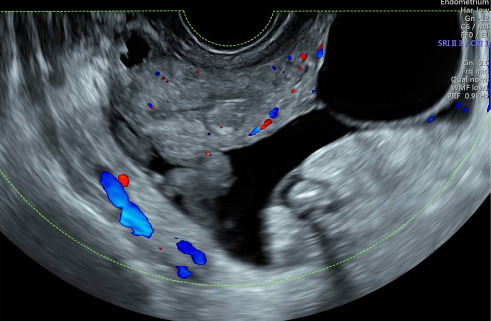

Genital tuberculosis (GT) is a rare but significant extrapulmonary tuberculosis form, often mimicking ovarian malignancy. We report a case of a 58-year-old woman with Sjögren's syndrome and rheumatoid arthritis, previously treated with infliximab, who presented with abdominal distension, weight loss, night sweats, and intermittent abdominal pain. Initial imaging and elevated CA-125 levels suggested ovarian cancer. However, intraoperative findings revealed a frozen pelvis with granulomatous inflammation, caseating granulomas, and Langhans' giant cells. Histopathological analysis and RT-PCR confirmed GT coexisting with a serous cystadenoma. GT should be considered in the differential diagnosis of pelvic masses, especially in immunocompromised patients. This case emphasizes the importance of thorough diagnostic evaluation using molecular, serological, and imaging techniques to avoid misdiagnosis and unnecessary surgical interventions. Prompt initiation of antituberculosis treatment led to significant clinical improvement. Early and accurate diagnosis of GT is crucial to prevent morbidity associated with misdiagnosis and to provide effective treatment. This case underscores the need for heightened clinical awareness and multidisciplinary approaches in managing complex cases where GT mimics malignancy, ensuring optimal patient outcomes.